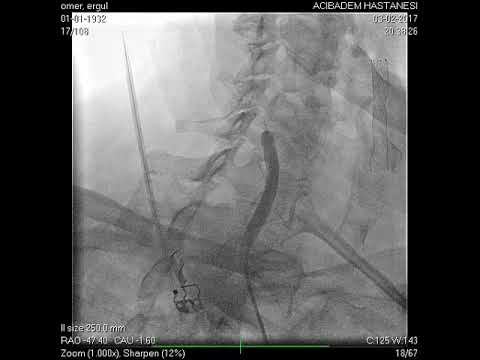

Anjiyografik İşlemler

Kapat